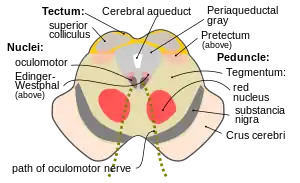

The principal regions of the midbrain are the tectum, the cerebral aqueduct, tegmentum, and the cerebral peduncles. Rostrally the midbrain adjoins the diencephalon (thalamus, hypothalamus, etc.), while caudally it adjoins the hindbrain (pons, medulla and cerebellum).[5] In the rostral direction, the midbrain noticeably splays laterally.

Sectioning of the midbrain is usually performed axially, at one of two levels – that of the superior colliculi, or that of the inferior colliculi. One common technique for remembering the structures of the midbrain involves visualizing these cross-sections (especially at the level of the superior colliculi) as the upside-down face of a bear, with the cerebral peduncles forming the ears, the cerebral aqueduct the mouth, and the tectum the chin; prominent features of the tegmentum form the eyes and certain sculptural shadows of the face.

The tectum (Latin for roof) is the part of the midbrain dorsal to the cerebral aqueduct.[3] The position of the tectum is contrasted with the tegmentum, which refers to the region in front of the ventricular system, or floor of the midbrain.

It is involved in certain reflexes in response to visual or auditory stimuli. The reticulospinal tract, which exerts some control over alertness, takes input from the tectum,[6] and travels both rostrally and caudally from it.

Cerebral aqueduct

The cerebral aqueduct is the part of the ventricular system which links the third ventricle (rostrally) with the fourth ventricle (caudally); as such it is responsible for continuing the circulation of cerebrospinal fluid. The cerebral aqueduct is a narrow channel located between the tectum and the tegmentum, and is surrounded by the periaqueductal grey,[9] which has a role in analgesia, quiescence, and bonding. The dorsal raphe nucleus (which releases serotonin in response to certain neural activity) is located at the ventral side of the periaqueductal grey, at the level of the inferior colliculus.

The nuclei of two pairs of cranial nerves are similarly located at the ventral side of the periaqueductal grey – the pair of oculomotor nuclei (which control the eyelid, and most eye movements) is located at the level of the superior colliculus,[10] while the pair of trochlear nuclei (which helps focus vision on more proximal objects) is located caudally to that, at the level of the inferior colliculus, immediately lateral to the dorsal raphe nucleus.[9] The oculomotor nerve emerges from the nucleus by traversing the ventral width of the tegmentum, while the trochlear nerve emerges via the tectum, just below the inferior colliculus itself; the trochlear is the only cranial nerve to exit the brainstem dorsally. The Edinger-Westphal nucleus (which controls the shape of the lens and size of the pupil) is located between the oculomotor nucleus and the cerebral aqueduct.[9]

Tegmentum

The midbrain tegmentum is the portion of the midbrain ventral to the cerebral aqueduct, and is much larger in size than the tectum. It communicates with the cerebellum by the superior cerebellar peduncles, which enter at the caudal end, medially, on the ventral side; the cerebellar peduncles are distinctive at the level of the inferior colliculus, where they decussate, but they dissipate more rostrally.[9] Between these peduncles, on the ventral side, is the median raphe nucleus, which is involved in memory consolidation.

The main bulk of the tegmentum contains a complex synaptic network of neurons, primarily involved in homeostasis and reflex actions. It includes portions of the reticular formation. A number of distinct nerve tracts between other parts of the brain pass through it. The medial lemniscus – a narrow ribbon of fibres – passes through in a relatively constant axial position; at the level of the inferior colliculus it is near the lateral edge, on the ventral side, and retains a similar position rostrally (due to widening of the tegmentum towards the rostral end, the position can appears more medial). The spinothalamic tract – another ribbon-like region of fibres – are located at the lateral edge of the tegmentum; at the level of the inferior colliculus it is immediately dorsal to the medial lemiscus, but due to the rostral widening of the tegmentum, is lateral of the medial lemiscus at the level of the superior colliculus.

A prominent pair of round, reddish, regions – the red nuclei (which have a role in motor co-ordination) – are located in the rostral portion of the midbrain, somewhat medially, at the level of the superior colliculus.[9] The rubrospinal tract emerges from the red nucleus and descends caudally, primarily heading to the cervical portion of the spine, to implement the red nuclei's decisions. The area between the red nuclei, on the ventral side – known as the ventral tegmental area – is the largest dopamine-producing area in the brain, and is heavily involved in the neural reward system. The ventral tegmental area is in contact with parts of the forebrain – the mammillary bodies (from the Diencephalon) and hypothalamus (of the diencephalon).

Cerebral peduncles

The cerebral peduncles each form a lobe ventrally of the tegmentum, on either side of the midline. Beyond the midbrain, between the lobes, is the interpeduncular fossa, which is a cistern filled with cerebrospinal fluid .

The majority of each lobe constitutes the cerebral crus. The cerebral crus are the main tracts descending from the thalamus to caudal parts of the central nervous system; the central and medial ventral portions contain the corticobulbar and corticospinal tracts, while the remainder of each crus primarily contains tracts connecting the cortex to the pons. Older texts refer to the crus cerebri as the cerebral peduncle; however, the latter term actually covers all fibres communicating with the cerebrum (usually via the diencephalon), and therefore would include much of the tegmentum as well. The remainder of the crus pedunculi – small regions around the main cortical tracts – contain tracts from the internal capsule.

The portion of the lobes in connection with the tegmentum, except the most lateral portion, is dominated by a blackened band – the substantia nigra (literally black substance)[9] – which is the only part of the basal ganglia system outside the forebrain. It is ventrally wider at the rostral end. By means of the basal ganglia, the substantia nigra is involved in motor-planning, learning, addiction, and other functions. There are two regions within the substantia nigra – one where neurons are densely packed (the pars compacta) and one where they are not (the pars reticulata), which serve a different role from one another within the basal ganglia system. The substantia nigra has extremely high production of melanin (hence the colour), dopamine, and noradrenalin; the loss of dopamine-producing neurons in this region contributes to the progression of Parkinson's disease.[11]